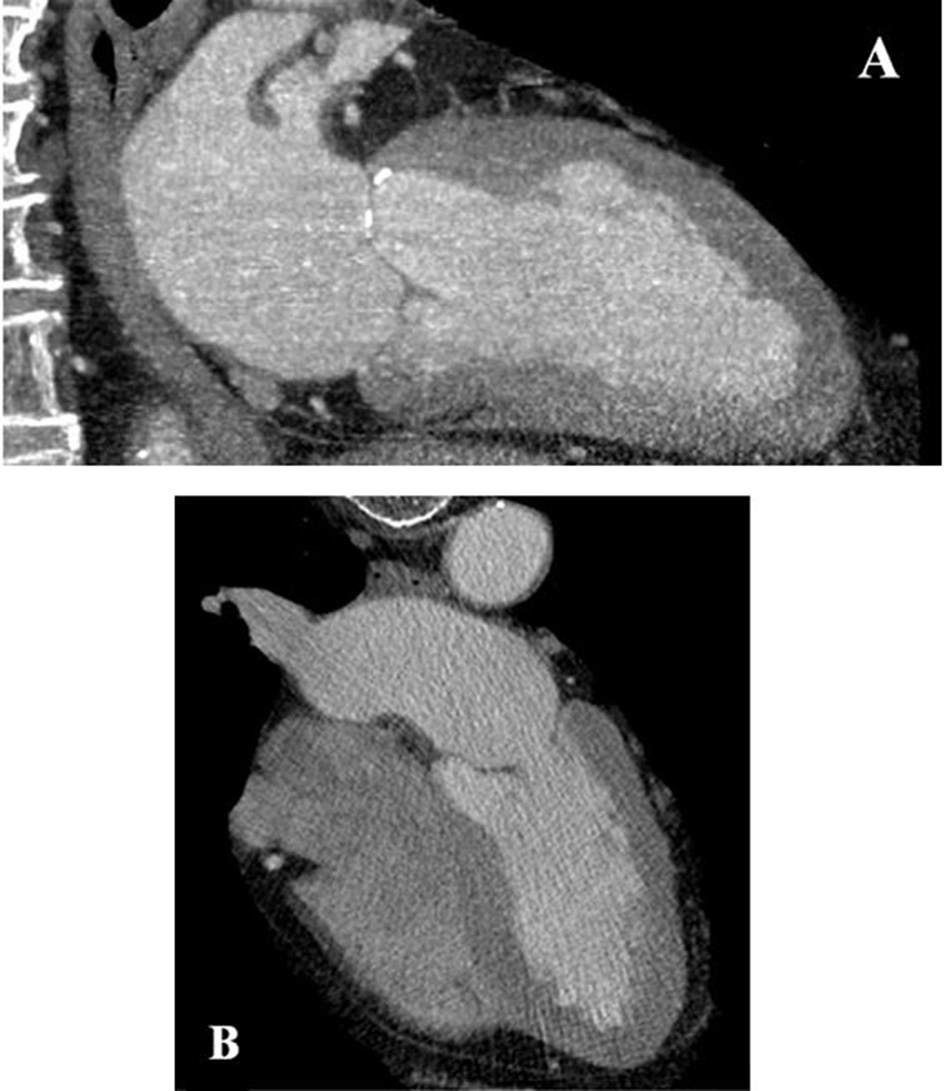

After 4 weeks, the patient was seen again in our outpatient clinic. Notably, triple therapy with dabigatran, clopidogrel, and aspirin had been well tolerated without evidence for significant bleeding. At this time, a cardiac computed tomography was performed, which failed to detect the LV thrombus described previously (Figure 3). Consequently, dabigatran therapy was stopped and dual antiplatelet therapy was continued for another 2 months. The patient was then switched to aspirin monotherapy and the surgical resection of the rectal neoplasm was performed in a peripheral hospital without any bleeding complications and stable hemoglobin values during and after the surgical resection.

Figure 3

Cardiac computed tomography of the left ventricle vertical view (A) and four chamber view (B) without any evidence for a left ventricular thrombus after 4 weeks.